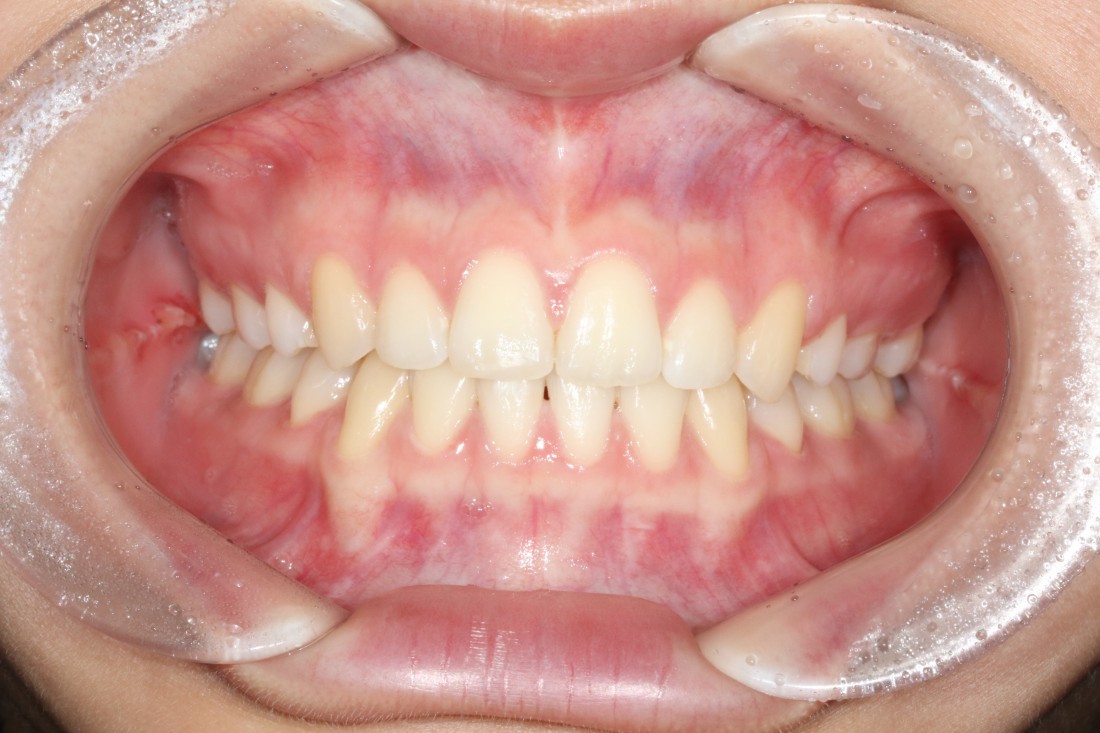

광주 교정치과는

200케이스 넘는 교정사례를

상세하게 공유해드리고 있기 때문에

실력을 믿고 맡기셔도 좋습니다.

더 다양한 교정 전/후 사례는

위의 사진을 클릭하시면

확인하실 수 있습니다.